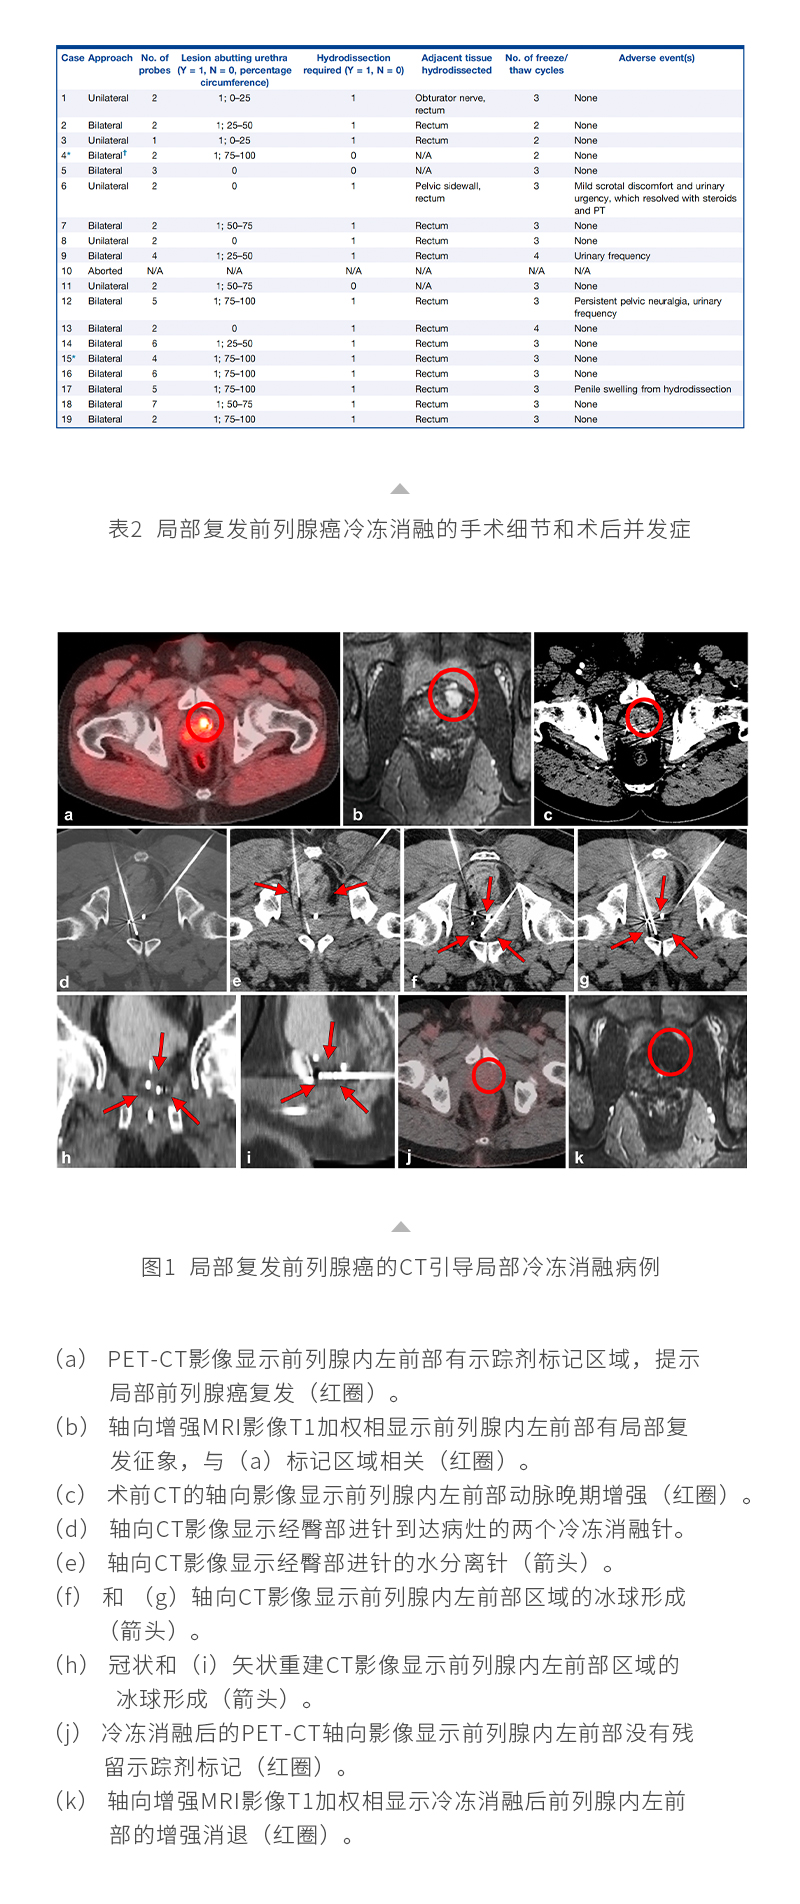

日本特黄特色a大片免费高清观看视频_亚洲午夜综合_一女被两男3p做爰视频_丰满少妇久久_欧美激情在线第一页_久久五月激情_亚洲成人激情在线_滚床单又黄又肉细节描写_日韩av综合在线观看_人妖一级片